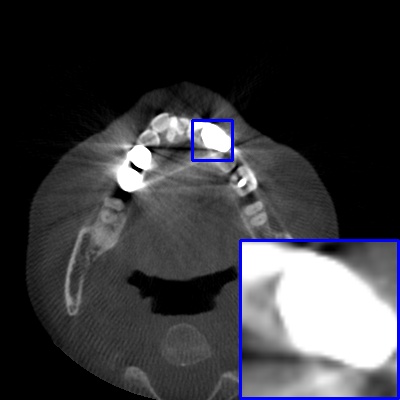

Figure 4: Comparison of MAR images by different methods on real-world MA image. The last image is the metal mask by selecting the pixel area over 2800HU in the MA image.

Results on real-world MAR. We also compare these methods on dental CBCT images with real-world metal artifacts. The visual results on one sample are shown in Fig. 4. We observe that our MARformer-T and MARformer-L well seperate the adjacent teeth and retain their shapes. This shows that our MARformers, though trained on synthetic data, are effective on real-world MAR.